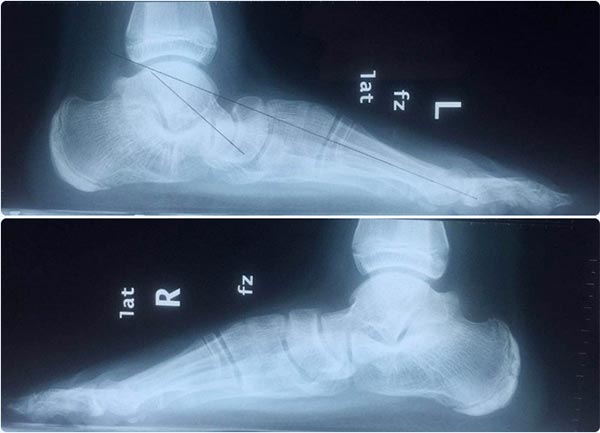

上圖為患者扁平足負(fù)重位影像學(xué)資料